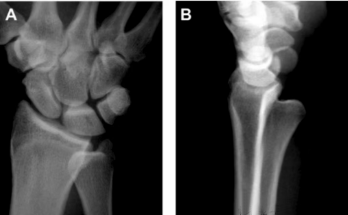

下尺橈關節脫位的診斷除依靠損傷機制、臨床表現及影像表現外,某些損傷也可提示存在下尺橈關節韌帶的損傷。包括蓋氏骨折、尺骨莖突基底部的骨折及CT橫斷位乙狀切跡的撕脫骨折。

從左到右:

蓋氏骨折、尺骨莖突基底部骨折、乙狀切跡撕脫骨折